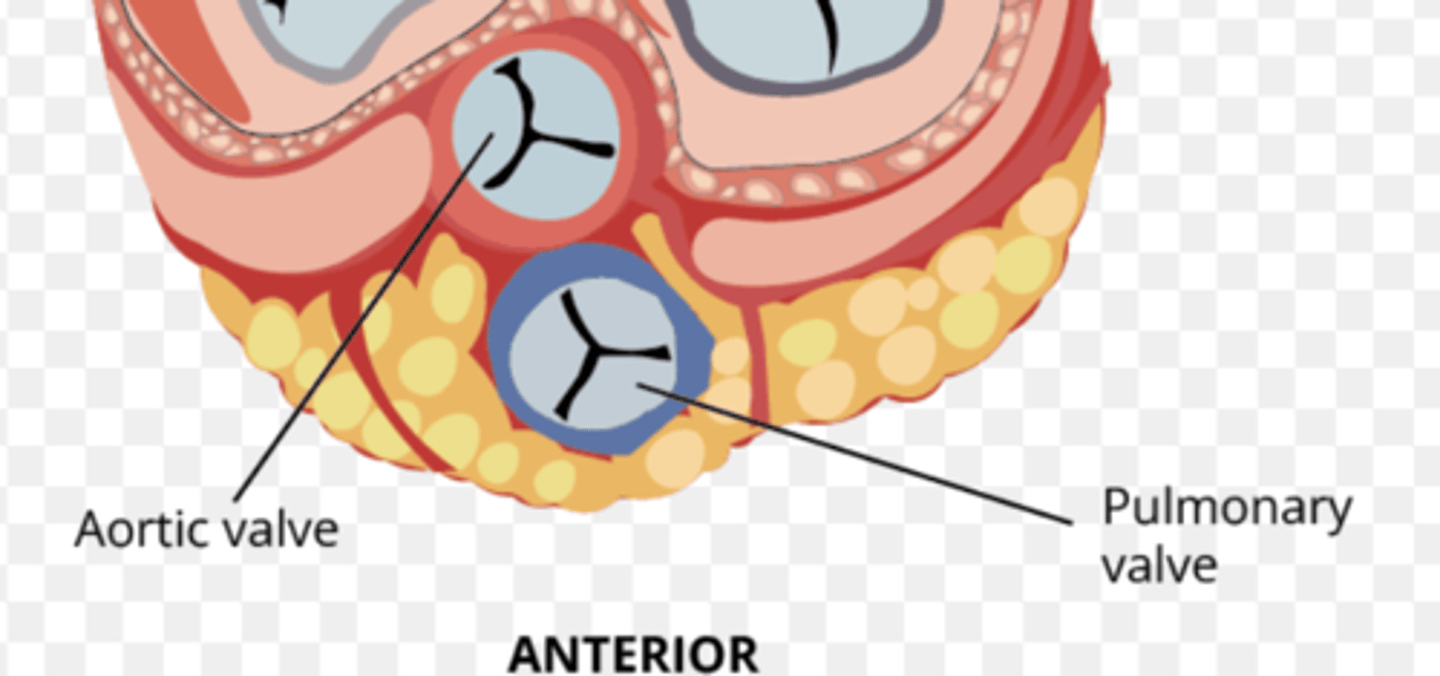

What are the positions of the pulmonary valve cusps?

Anterior

Right

Left

What is the valve to prevents reflux in the aorta?

Aortic valve

What are the 3 parts of the aortic valve?

3 semilunar cusps

posterior

right

left

POSITION IS DIFFERENT THAT IN THE PULMONARY (posterior vs anterior)

What is the structure of the cusps of the aortic valve?

. Nodules

. Lunules

. Small holes for the coronary arteries

MAIN DIFFERENCE WITH PULMONARY VALVES ARE THE SMALL HOLES FOR THE CORONARY ARTERIES.

What is the 1st branch of the aorta?

The small holes in the aortic valve cusps to irrigate the coronary arteries.